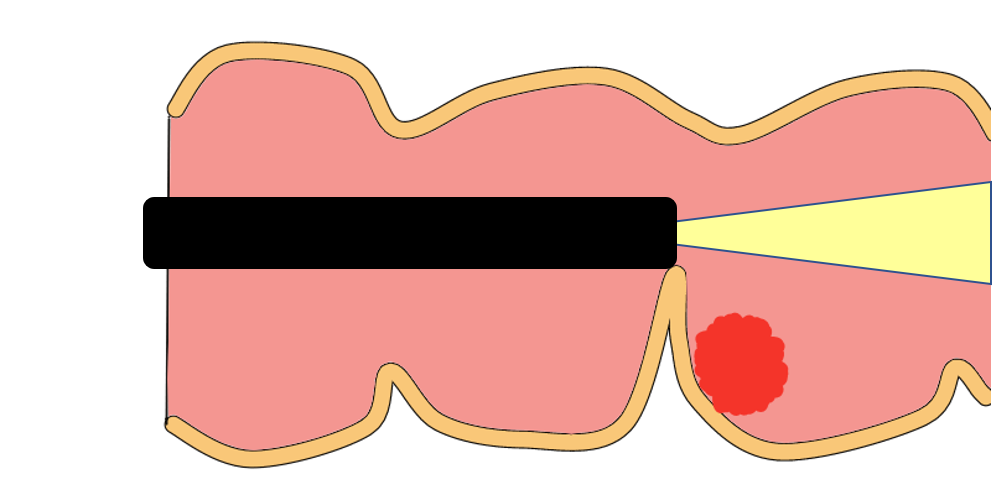

大腸粘膜には痛みの神経がありません。カメラがこすれる程度では痛みにはなりません。しかし下図のように、押し込むようにカメラ入れる場合には腸を突っ張る形になり、腸を引っぱったりするため痛みが強くなります。またカメラによる腸管穿孔(腸管が裂けてしまうこと)が起こりやすくなります。

当院では下図のように矢印方向にカメラを振ることで、腸管をカメラで折りたたむようにします。なるべく腸を突っ張らせないように軸を保持する軸保持短縮法によって検査を行っています。腸の変形が少ないため痛みの少ない検査になります。

大腸という臓器は内腔にヒダが多く存在します。カメラで観察すると長いトンネルにふすまがたくさんあるように見えます。このヒダは中途半端に開いたふすまのようなっています。内視鏡は前方はよく見えますが真横などは死角となるため、このふすまの裏にあるポリープは見逃されがちです。

先端フードは図のようにカメラの先端に装着します。帽子の”つば”のようにヒダをめくるように観察が可能になります。